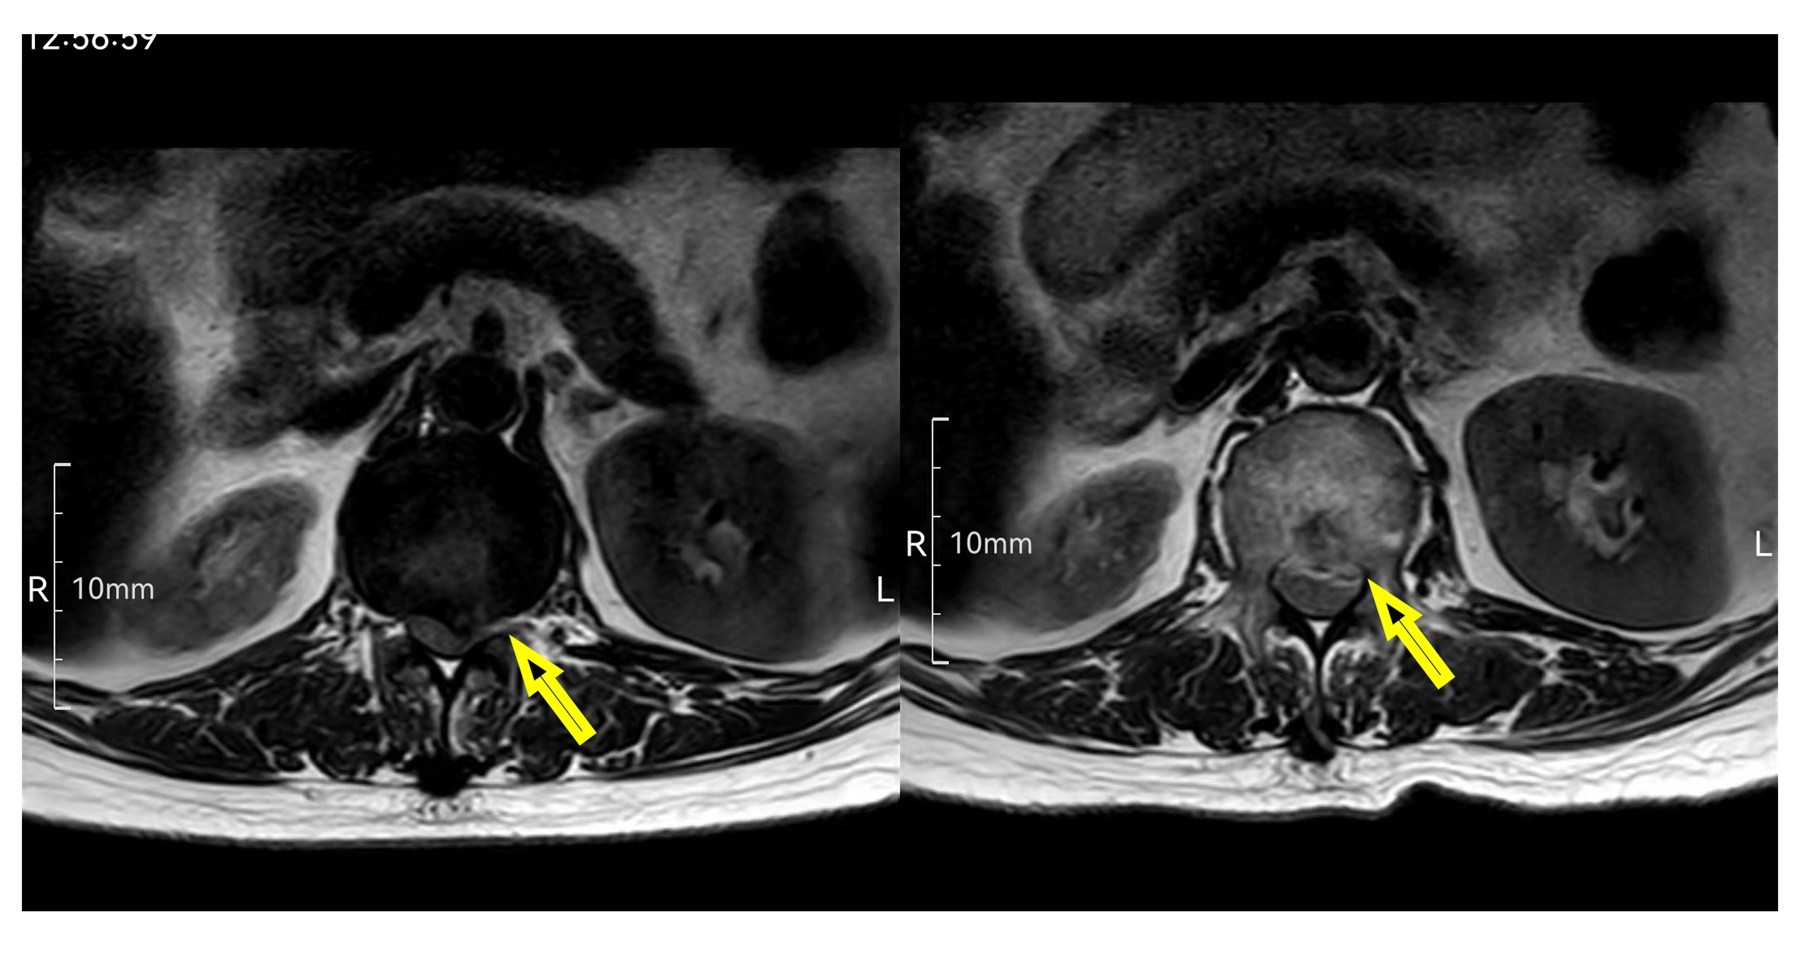

图2.术前(左图)术后(右图)腰椎磁共振横截面对比,显示突出髓核已被摘除。